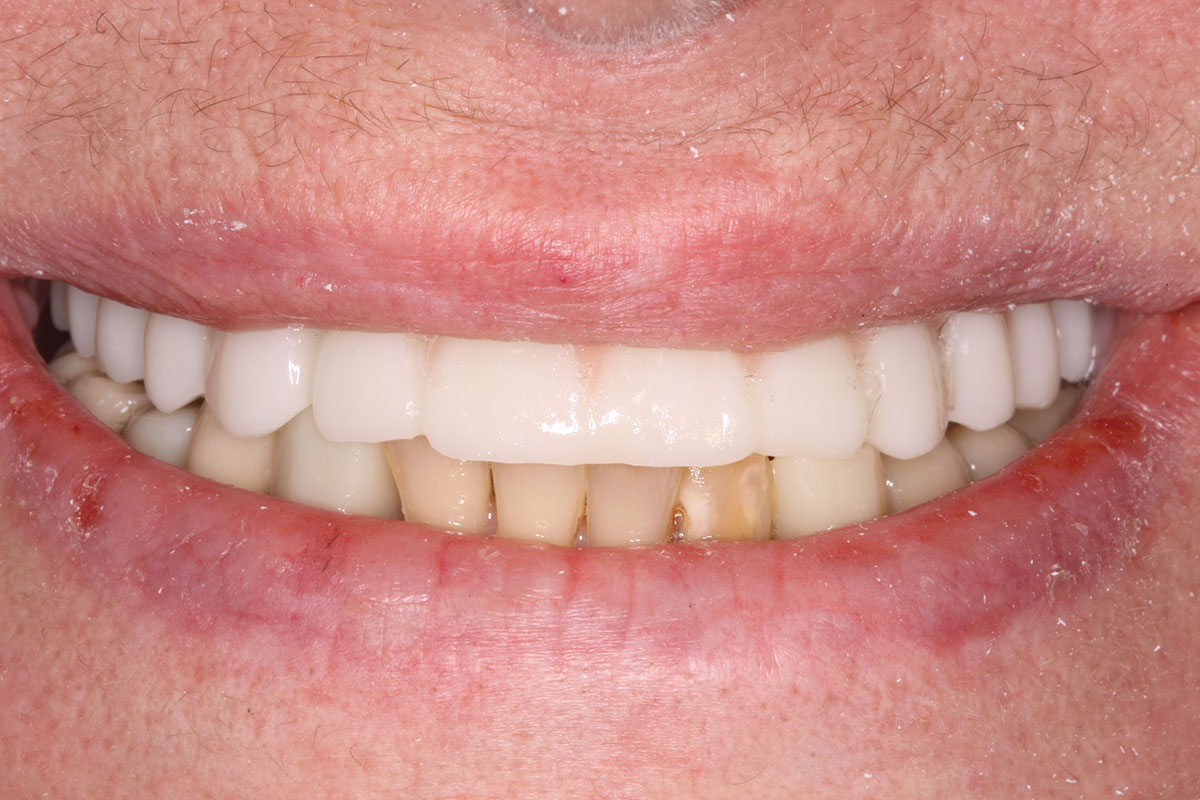

The prosthesis fit precisely on the multi-unit abutments, and multi-unit screws were used to secure the prosthesis in place at 20 Ncm (Figure 18 through Figure 20). The screw-access holes were filled, and the patient was instructed on dietary restrictions and adherence to a soft diet. Instructions for oral hygiene were given, and the patient was advised to use a water flosser daily. Analgesics included ibuprofen 800 mg, and for antibiotics, amoxicillin 500 mg three times a day was prescribed.

Fig 18. Implants and provisional maxillary prosthesis in place, the same day as surgery.

Figure 18

Fig 19. The patient’s smile display, the same day as surgery.

Figure 19